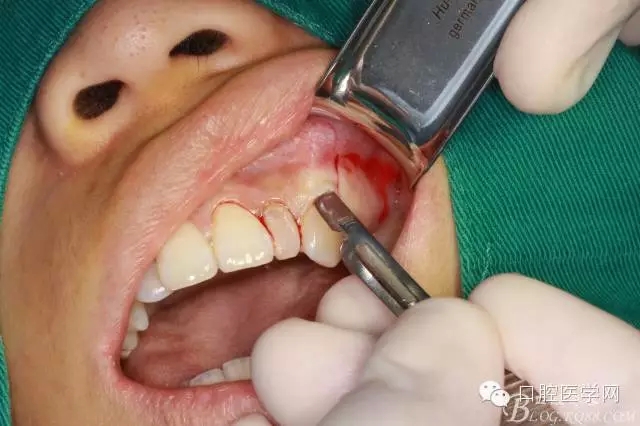

垂直切口

水平切口